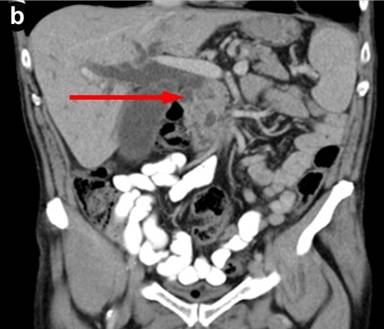

The patient then developed painless obstructive jaundice four months after the procedure. As the clinical features changed and became more sinister, CT scan was repeated, following which a referral was made to the tertiary regional HPB unit. The pre-bypass CT had shown inflammation in the groove with cystic changes in the duodenal wall. A repeat CT at our centre showed a major difference in that there was significant dilatation of the bile duct with a stenosis at the cystic duct insertion site, but the pancreatic duct was not significantly dilated. This was followed by a failed ERCP due to duodenal stenosis hence percutaneous transhepatic cholangiogram and biliary drainage was carried out. MRCP showed a small non enhancing area of low T1 signal within the pancreatic head surrounding the intra-pancreatic common bile duct extending to the ampulla of uncertain significance. CT and MRI scans revealed deleted a soft tissue mass in the head of the pancreas, abutting his superior mesenteric vein (Figures 1 and 2).

|

Figure 2. Pre-operative MRCP. a. Coronal MRCP images illustrating soft tissue mass in head of pancreas and dilatation of the intra and extrahepatic biliary tree. b. Coronal MRCP illustrating intra and extrahepatic biliary duct dilatation. |